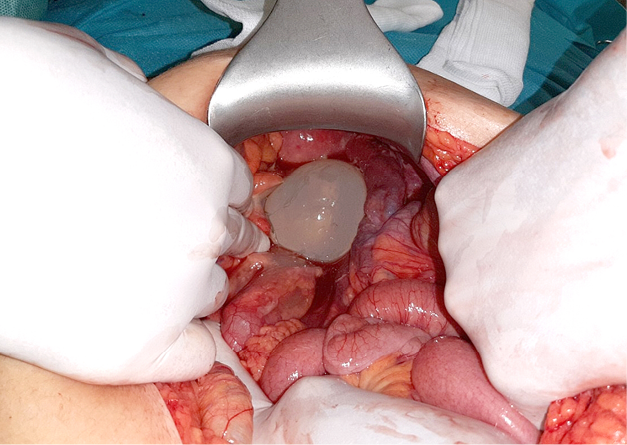

Median laparotomy was made verifying the echinococcal cysts of the liver. On the visceral side of the fifth segment, an irregular change with adhesions and fibrosis is recorded. It looks alike a periphery of a pericyst above which is the persistant cyst of the V–VI segment. A small adenomatous change of the visceral side of the fifth segment is also noted which is 2 cm in diameter. One cystic formation in germinative membrane only, was found in the small pelvis surrounded with inflamed parts of sigmoid colon, part of the greater omentum and uterus (Figure 4). Evacuation of the cyst was performed. Also, an evacuation of the cysts was performed from the liver. Cysts were opened, the germinative membranes were evacuated and a reduction of pericysts after Papadimitriou was performed. Two omental flaps by the greater omentum were made and inserted in residual cavities of the liver. Two passive drains were applied. An excision of the granulated adenomatous change from the surface of the fifth segment was performed. The drains were extracted on the third and fourth postoperative day.

Figure 4. Cystic formation in germinative membrane surrounded with inflamed parts of sigmoid colon,

part of the greater omentum and uterus